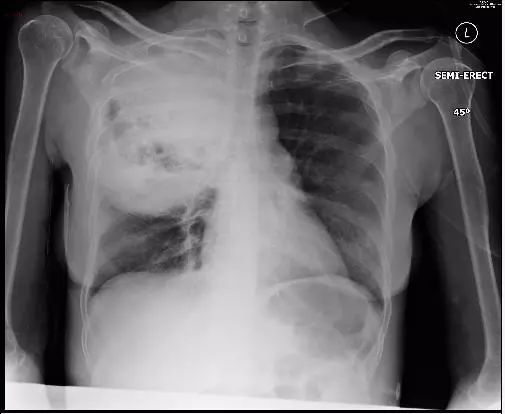

患者急性起病,发热,咳嗽,咳痰,痰液粘稠。

诊断啥?

肺炎克雷伯杆菌,是肺炎常见细菌,典型的影像学表现是叶间裂下坠。什么是叶间裂下坠?书上只有文字,我也可以意会到,然而画面很模糊。多年以后,我才突然秒懂!

一般情况下,克雷伯杆菌肺炎的影像学表现与其他细菌性肺炎相似, 仅根据影像鉴别相当的诊断困难,但是,知道其特点,才能发现典型的患者,有时候可以更好的早期诊断,减少抗生素滥用,为人民服务!